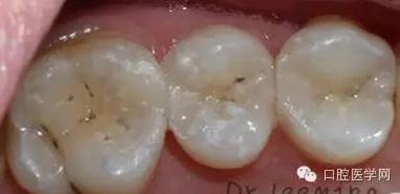

這個患者是我的小粉絲,女兒大部分的齲齒都是我處理好的,家長很滿意。這次媽媽終于有時間來看牙齒,昨天充填了三顆二類洞,術后照片看,對于第一磨牙最后的充填效果,狠狠的給自己的熱情潑了冷水,第一磨牙窩溝上的齲是沒有處理的,有些覆蓋在上面的樹脂,是因為塑形的時候,把樹脂推過去的,術后只是調磨了一下咬合高點,沒有精修和拋光,也打算復診回來,看看第一磨牙的情況,再選擇重新的充填,然后整體精修拋光。

下面也分享一下個人對于昨天病例的一些充填細節(jié),純屬根據理論和自己的臨床發(fā)現(xiàn)總結得出來的心得。

充填:二類洞先把鄰面堆起來,注意,一些人會把鄰面邊緣嵴堆的太高,造成較多的調磨,和調磨后破壞本身充填形態(tài)。充填前觀察前后鄰牙的邊緣嵴高度,作為參考。變成一類洞后,就分層塑形(洞不深,可以不分層),到雙面的二類洞的話(例如病例上的56,共同的牙體缺損隙,雙面二類洞屬于個人理解)我個人比較建議先把缺損小的恢復起來,這樣子的話,可以更好的已缺損小的作為參考,更好的恢復鄰面,還有因為,缺損小,成型系統(tǒng)更容易挾持邊緣嵴,更好的恢復本身的鄰面。

拋光:每次恢復一顆牙齒的鄰面或者充填好,必須都要拋光條拋光,一些比較緊的,慢慢輕微加壓,一邊加壓一邊左右拉扯,作拋光的左右來回運動,慢慢就可以充分拋光,因為你成型的時候,成型片的厚度和拋光條是相差不多,不過一些也比成型片厚。

拆障用剪刀,充填好,精修,咬合高點處理。一般24小時拋光。